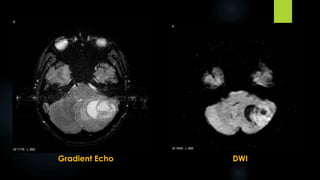

Medulloblastoma (contd.)

 MRI:

 Hypointense on T1

 Variable hypo‐ to hyperintense on T2

 Variable enhancement

 restricted diffusion on diffusion-weighted imaging

T1

T1 + C

FLAIR

Gradient Echo DWI